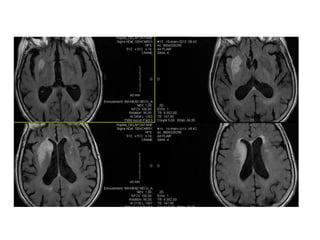

Mismatch diffusion-FLAIR

• Il est 7h30… Attente de

l’hémostase

• 7h45 : INR = 1,47

• 29 ans •Infarctus sylvien gauche étendu • De cause cardioembolique • Présence d’un mismatch Diffusion/FLAIR MAIS

• 27.